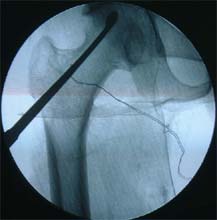

股骨头缺血性坏死MRI显示坏死区 微创手术方法,刮除死骨